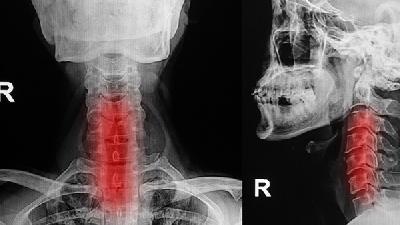

咽炎的可能原因